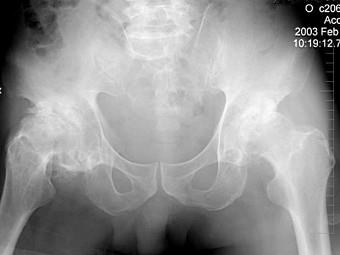

问题 60岁男性患者,因双髋关节反复疼痛2年多,无明显外伤史,行X线摄片如图示,最可能的诊断是 ( )

选项 A、双髋关节结核 B、双髋关节化脓性关节炎 C、双髋关节创伤性关节炎 D、双髋关节特发性骨关节病 E、双髋关节退行性骨关节病

答案 E